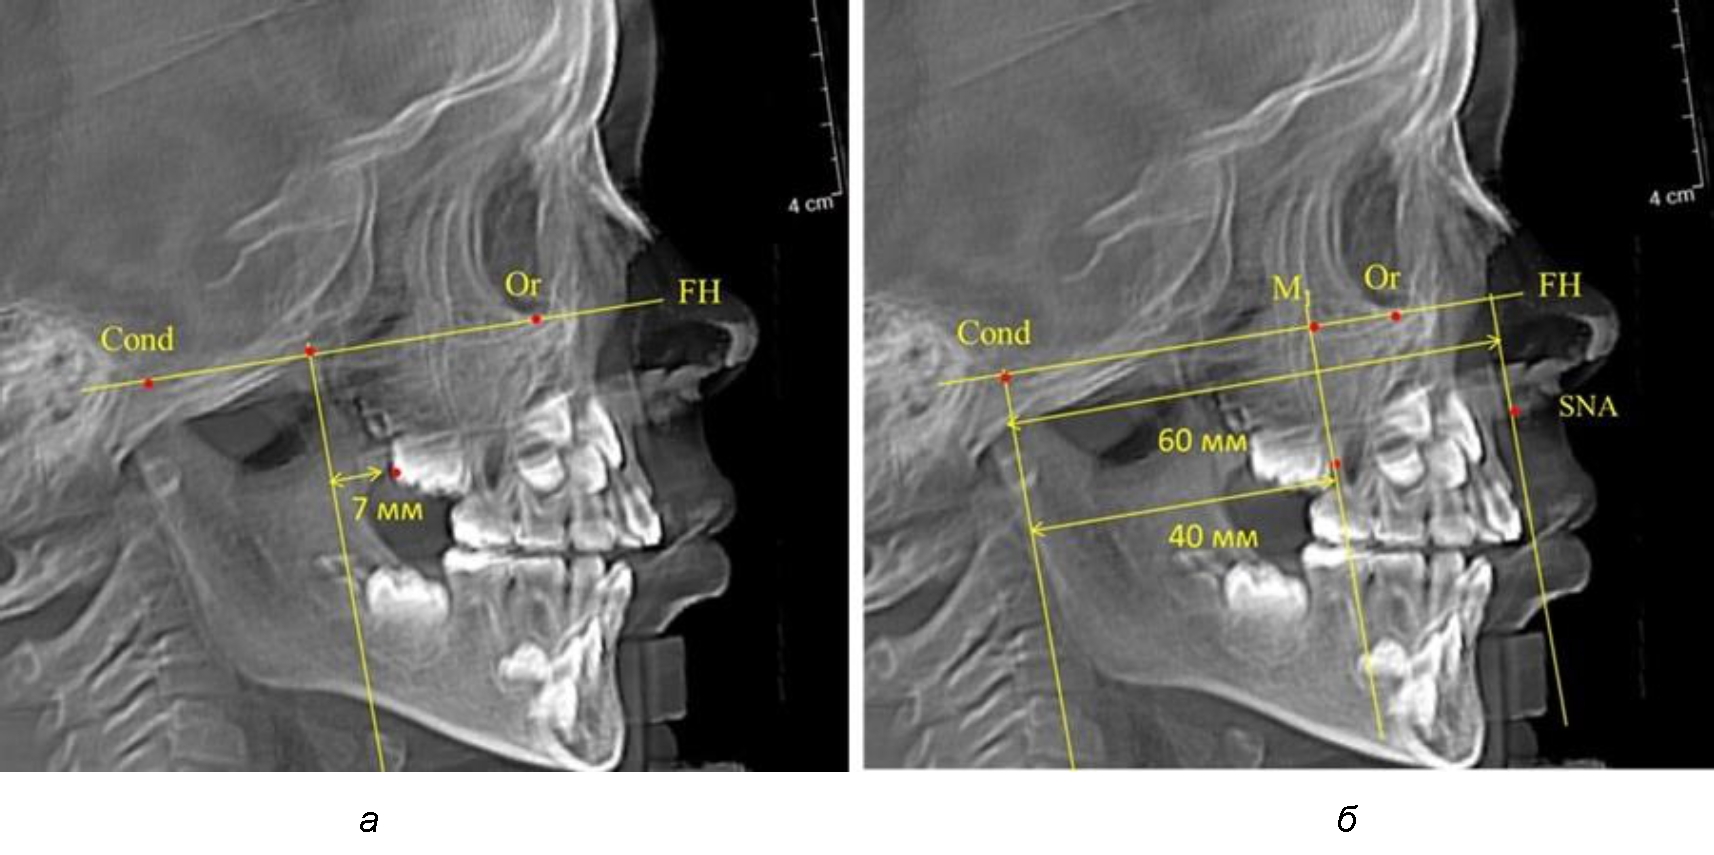

Рис. 1. Метод определения положения первых верхних моляров по Ralph E. McDonald (а) и по предложенному методу (б)

Второй частью исследования был анализ положения первых постоянных моляров в различные периоды сменного прикуса. На телерентгенограммах детей периода прикуса молочных зубов дистальная поверхность зачатка первого постоянного моляра отстояла от крыловидной вертикали на величину, составляющую около 7 мм, что было близким по значению к данным R. E. McDonald. Сагиттальный размер гантического отдела составлял около 60 мм, а его отношение к кондилярно-молярной глубине – 1,5 (рис. 4).

При проведении анализа к Франкфуртской горизонтали проводили передний и задний перпендикуляры. Передний спинальный перпендикуляр проходил через выступающую точку передней носовой ости (spina nasalis anterior – SNA), а задний суставной перпендикуляр опускали из кондилярной точки Cond. Молярный перпендикуляр проводили через медиальную поверхность первого постоянного моляра. Указанная вертикаль отделяла замещающие зубы постоянного прикуса от добавочных зубов (постоянных моляров), что вполне логично для анализа положения первых постоянных моляров в гнатическом комплексе (рис. 1).

Согласно указанному методу на рентгенограммах проводили Франкфуртскую горизонталь. Учитывая мнения специалистов относительно ориентиров для построения и вариабельность положения наружного слухового прохода, в качестве задней точки использовали верхнюю выпуклость суставной головки нижней челюсти («Cond»). Передняя точка традиционно располагалась на нижнем крае глазницы и определялась как орбитальная точка Or.

Находили положение точки Pt, которая располагалась на пересечении нижнего края круглого отверстия и задней стенки крыловидно-верхнечелюстной щели, и перпендикулярно к Франкфуртской горизонтали проводили крыловидную вертикальную линию, которую принято обозначать как плоскость PTV. Расстояние от крыловидной вертикальной плоскости PTV до дистальной поверхности верхнего первого постоянного моляра определяло его положение, которое, по мнению R. E. McDonald, соответствовало возрасту пациента, увеличенному на 3 мм.